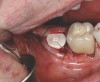

Fig 15. Grafting with particulate mineralized cortico-cancellous allograft and placement of PEEK healing abutment.

Figure 15

Implant insertion (5.5 mm x 13 mm NobelActive®, Nobel Biocare, nobelbiocare.com) gave excellent primary stability, was level with the residual buccal bone, and achieved an ISQ reading of 74 (Figure 14). Lingual bone contouring (to avoid abutment impingement) was followed with implant gap grafting, which included the mesiobuccal root defect and adjacent extraction site, using mineralized particulate cortico-cancellous allograft (enCore®, Osteogenics Biomedical). A 7 mm x 8 mm poly-ether-ether-ketone (PEEK) healing abutment was inserted and the access opening filled with PTFE tape (Figure 15). A single layer of dHACM (Figure 16) was inserted on the bone graft with tissue forceps and saturated with saline to seal the implant-soft-tissue interface. Suturing with 4-0 chromic gut secured the site, using inverse "figure 8" at the anterior and interrupted sutures at the posterior margin (Figure 17).